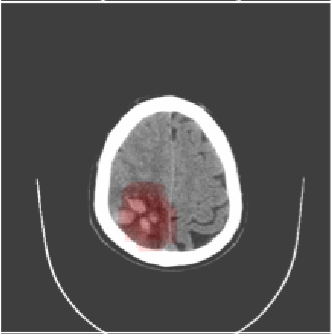

Inverse Problems in Neuroscience: Susceptibility Tensor Imaging

Inverse Problems in Radiology